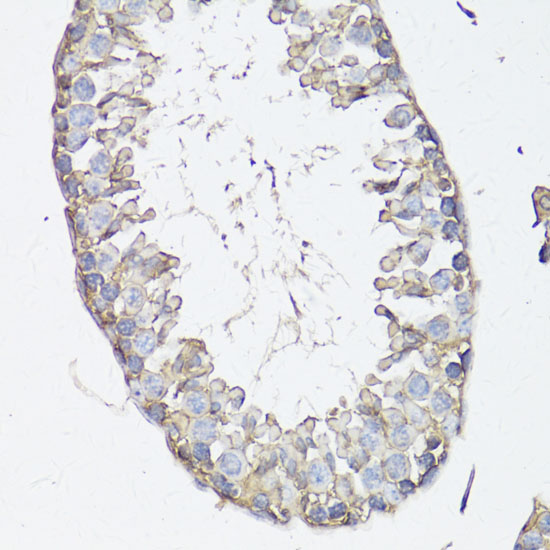

Immunohistochemistry of paraffin-embedded rat testis using MRP4/ABCC4 antibody.

Immunohistochemistry of paraffin-embedded mouse testis using MRP4/ABCC4 antibody.